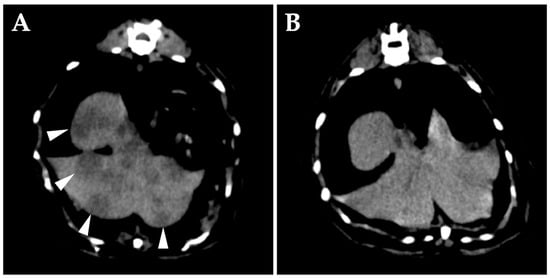

On day 176, the patient developed an unstable appetite and nasal obstruction sounds. Intraoral examination revealed swelling of the soft palate. Blood tests revealed no particular abnormalities. Contrast-enhanced whole-body CT under anesthesia showed unchanged filling of bilateral tympanic bullae and no obvious bony abnormalities. A mass lesion with heterogeneous contrast enhancement was found on the ventral side of the right tympanic bulla, almost completely obstructing the nasopharyngeal passage (Figure 4A). The right medial retropharyngeal lymph node was contiguous with the ventral lesion of the tympanic bulla and showed heterogeneous contrast enhancement. Multiple contrast-enhanced mass lesions were noted in the liver (maximum diameter, 18 mm) (Figure 4C,D). No obvious intrathoracic or intra-abdominal organ abnormalities were apparent other than in the liver. MRI of the head revealed no obvious meningeal lesions and other abnormalities of the brain (Figure 4B). The tentative diagnosis was spread of lymphoma in the right middle ear to the Eustachian tube and formation of a mass in the nasopharyngeal region.

Figure 4. Transverse images on day 176. (A,B) Computed tomography (CT) (A) and magnetic resonance imaging (B) of the head at the level of the middle ear. A mass lesion showing heterogeneous enhancement from contrast media is present in the nasopharyngeal region (arrow). (C,D) On CT of the abdomen at the level of the liver, multiple hypo-attenuating, contrast-enhanced nodules are present in the liver (arrowheads) ((C) pre-contrast; (D) post-contrast).